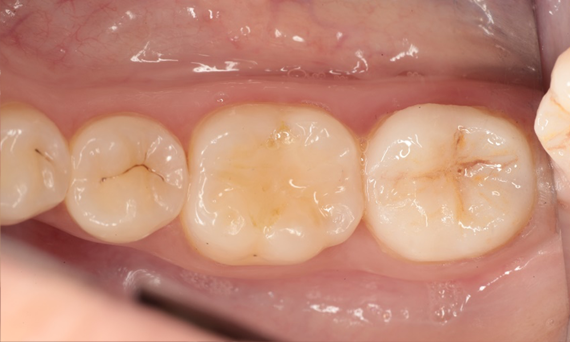

Restauration de la deuxième molaire mandibulaire en consultation

Couronne partielle CEREC Tessera

Une deuxième molaire mandibulaire sensible présentait des fissures ainsi qu’une restauration composite de classe I étendue sur la face vestibulaire. Conformément au concept mini-invasif, une couronne partielle CFAO a été planifiée, fabriquée et collée à l’aide du CEREC Tessera en une seule visite.

Avant : Restauration en amalgame défaillante nécessitant un remplacement. Patient se plaignant de sensibilité et dent présentant de multiples fissures.

Après : Restauration d’une couronne partielle CFAO réalisée en consultation avec la vitrocéramique CEREC Tessera Advanced Lithium-Disilicate.